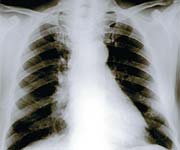

Unnecessary X-rays

When x-rays were discovered, no one knew the long-term effects of ionizing radiation. In the 1950s, monthly fluoroscopic exams at the doctor’s office were routine, and you could even walk into most shoe stores and see x-rays of your foot bones. We still do not know the ultimate outcome of our initial fascination with x-rays.

In those days, it was common practice to x-ray pregnant women to measure their pelvises and make a diagnosis of twins. Finally, a study of 700,000 children born between 1947 and 1964 in 37 major maternity hospitals compared the children of mothers who had received pelvic x-rays during pregnancy to those of mothers who did not. It found that cancer mortality was 40% higher among children whose mothers had been x-rayed.94

In present-day medicine, coronary angiography is an invasive surgical procedure that involves snaking a tube through a blood vessel in the groin up to the heart. To obtain useful information, x-rays are taken almost continuously, with minimum dosages ranging from 460 to 1,580 mrem. The minimum radiation from a routine chest x-ray is 2 mrem. X-ray radiation accumulates in the body, and ionizing radiation used in x-ray procedures has been shown to cause gene mutation. The health impact of this high level of radiation is unknown, and often obscured in statistical jargon such as, “The risk for lifetime fatal cancer due to radiation exposure is estimated to be 4 in 1 million per 1,000 mrem.”95

Dr. John Gofman has studied the effects of radiation on human health for 45 years. A medical doctor with a PhD in nuclear and physical chemistry, Dr. Gofman worked on the Manhattan Project, discovered uranium-233, and was the first person to isolate plutonium. In five scientifically documented books, Dr. Gofman provides strong evidence that medical technology—specifically x-rays, CT scans, and mammography and fluoroscopy devices—are a contributing factor to 75% of new cancers. In a nearly 700-page report updated in 2000, “Radiation from Medical Procedures in the Pathogenesis of Cancer and Ischemic Heart Disease: Dose-Response Studies with Physicians per 100,000 Population,”96 Gofman shows that as the number of physicians increases in a geographical area along with an increase in the number of x-ray diagnostic tests performed, the rate of cancer and ischemic heart disease also increases. Gofman elaborates that it is not x-rays alone that cause the damage but a combination of health risk factors that include poor diet, smoking, abortions, and the use of birth control pills. Dr. Gofman predicts that ionizing radiation will be responsible for 100 million premature deaths over the next decade.

In his book, “Preventing Breast Cancer,” Dr. Gofman notes that breast cancer is the leading cause of death among American women between the ages of 44 and 55. Because breast tissue is highly sensitive to radiation, mammograms can cause cancer. The danger can be heightened by other factors, including a woman’s genetic makeup, preexisting benign breast disease, artificial menopause, obesity, and hormone imbalance.97